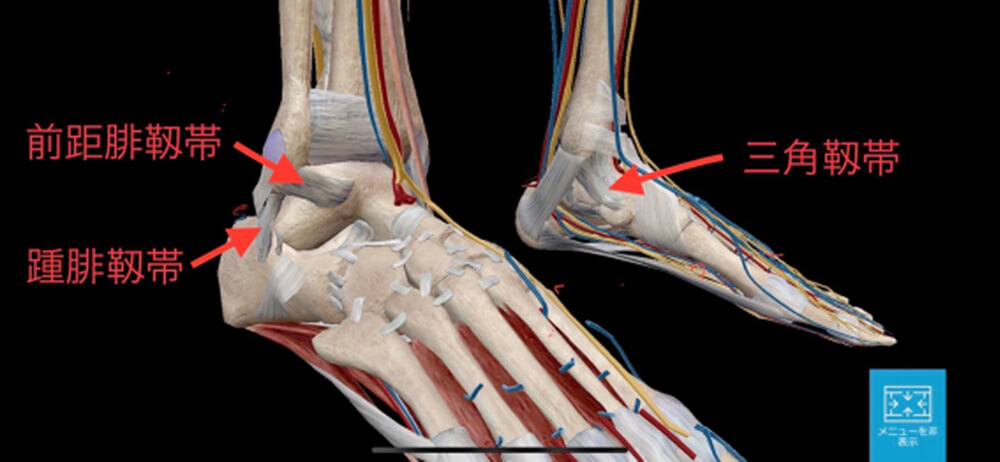

解剖

足関節には内側の三角靱帯と、外側の前距腓靱帯・踵腓靱帯があります。

足関節